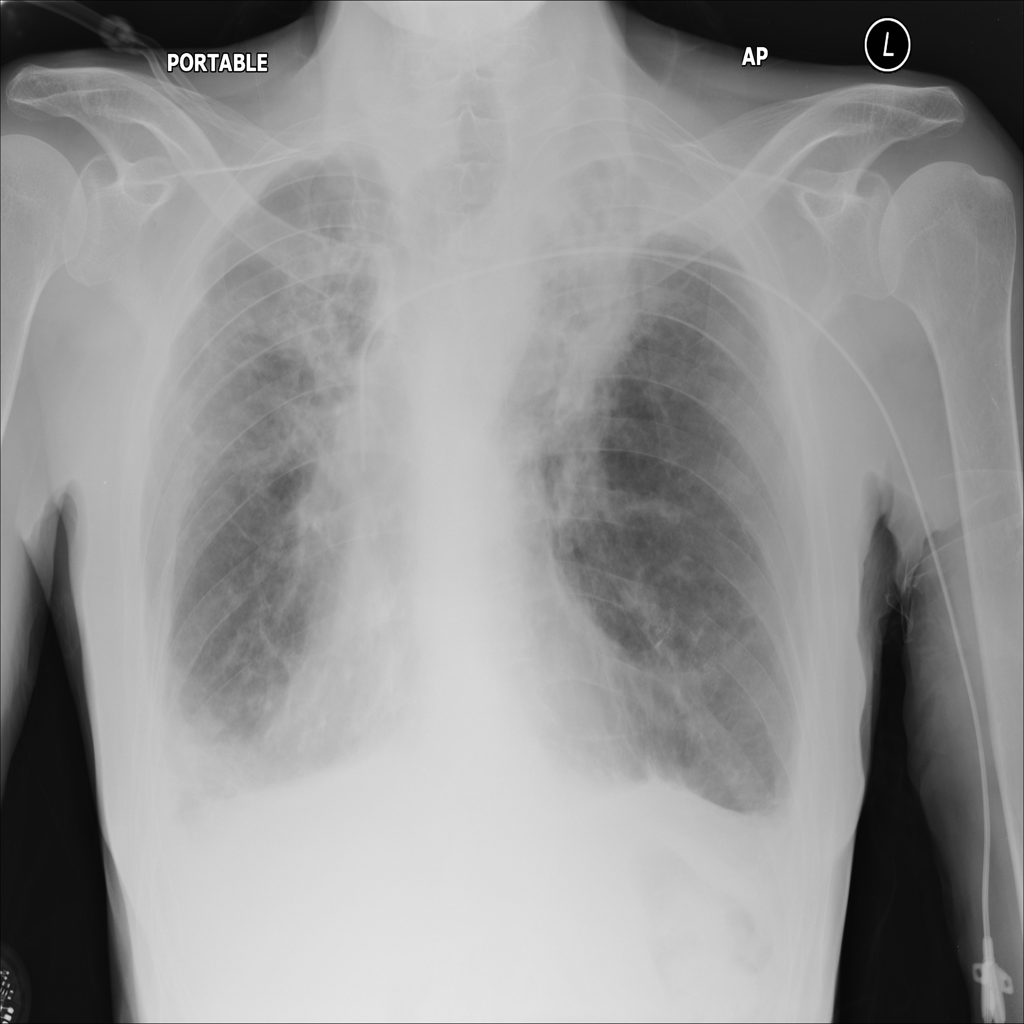

Consolidation

Consolidation refers to air-space filling that makes part of the lung appear denser on imaging.

Showing up to 90 reference images for Consolidation.

PAT-04B3 · IMG-001Consolidation

PAT-04B3 · IMG-001

PA